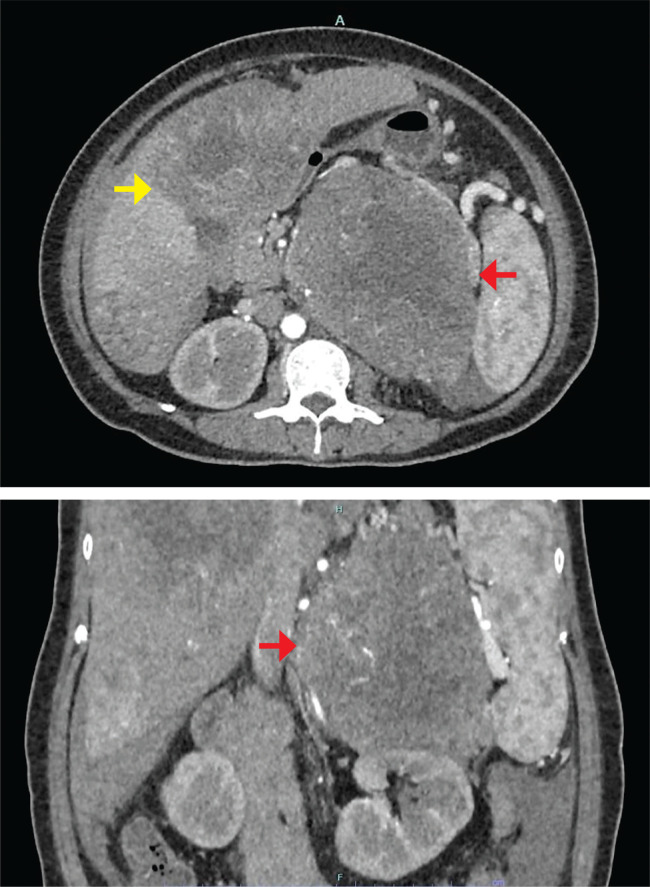

Adrenocortical carcinoma (ACC) is a rare malignant tumour from the adrenal cortex. Half of the cases are functional, with ACTH-independent autonomous cortisol production being the most common. It is rare for ACC to present with markedly elevated metanephrine levels, characteristic of pheochromocytoma. We report a case of a large functioning adrenal tumour with overlapping biochemical features of ACC and pheochromocytoma. Biopsy confirmed the histopathological diagnosis of metastatic ACC.